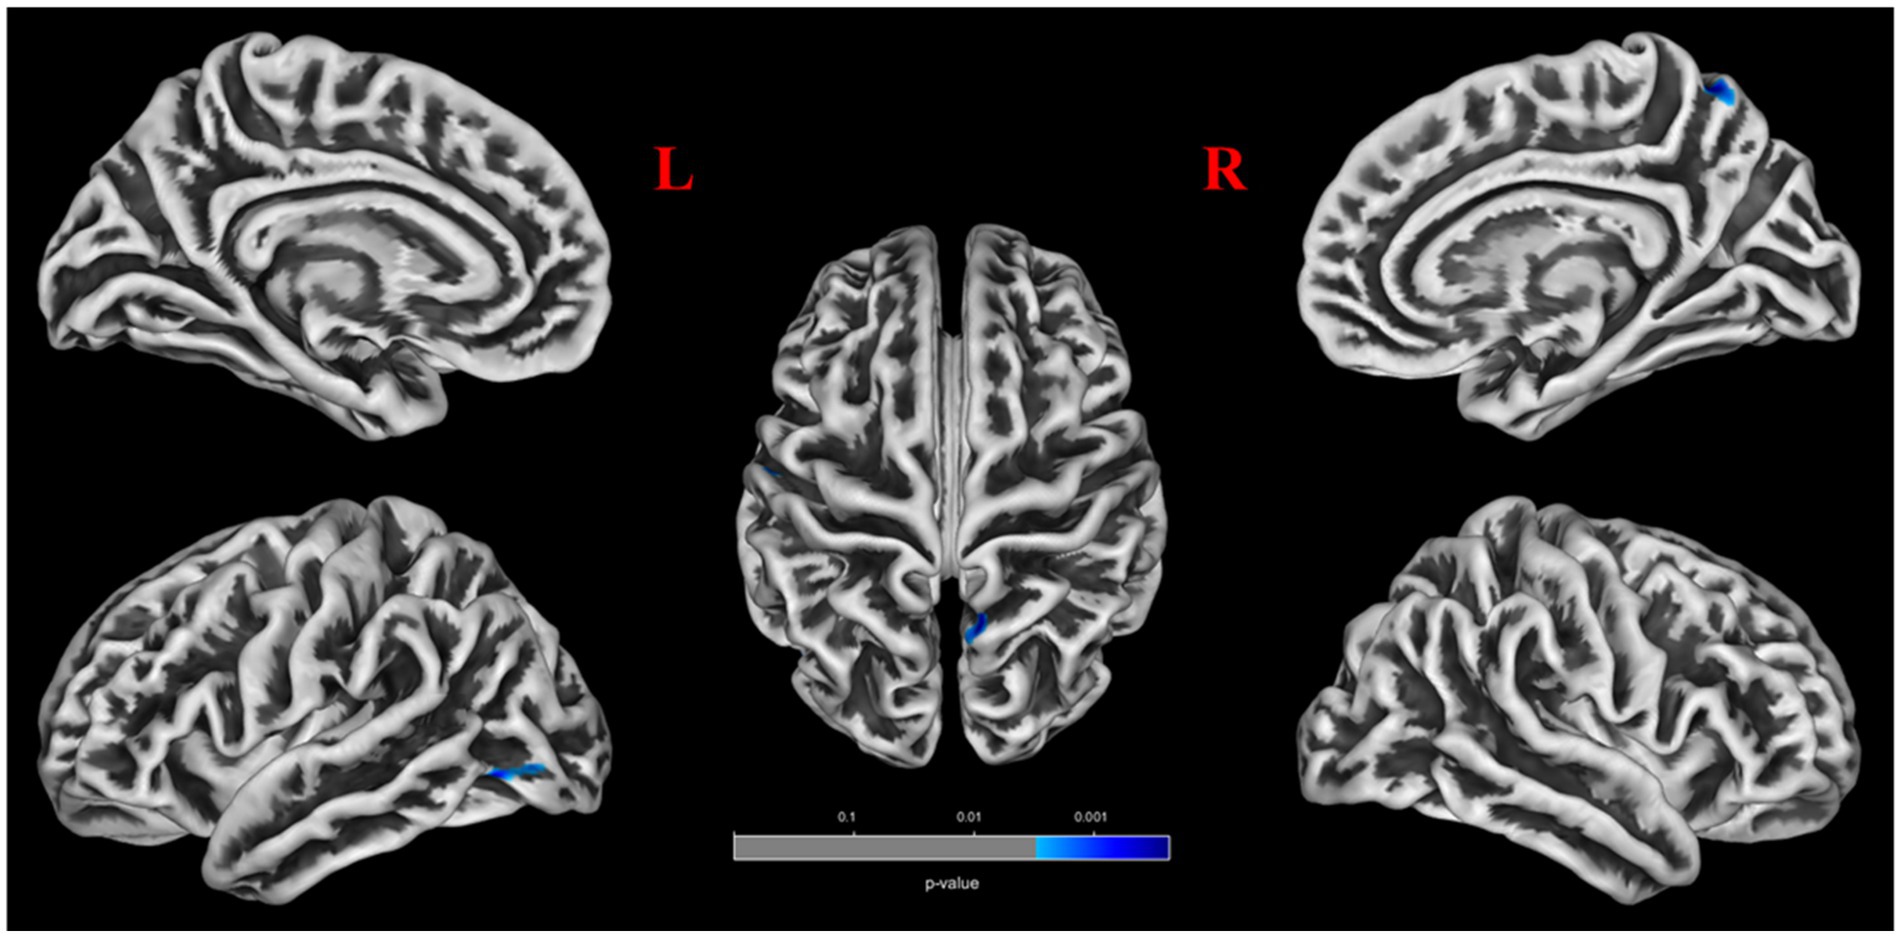

No significant differences were found between patients with POAG and HCs in global GM volume, WM volume, and CSF volume after adjusting for TIV, age, sex, and education years (Figure 2). However, patients with POAG exhibited reduced cortical thickness in three clusters compared to HCs, including the left middle occipital gyrus (MOG.L), left postcentral gyrus (PoCG.L), and right precuneus (PCUN.R) (p < 0.05, FDR corrected) (Figure 2, Table 4). No clusters of sulcal depth and increased cortical thickness were observed in patients with POAG compared to HCs. Additionally, no significant differences were found in the whole-brain VBM and DBM analyses between patients with POAG and HCs (p > 0.05, FDR corrected).

Figure 2

Comparison of the cortical thickness of patients with POAG and HCs.

SBM, surface-based morphometry; POAG, Primary open-angle glaucoma; HCs, healthy controls. The cool color regions representing significantly thinner cortical regions in patients with POAG (FDR, voxels p < 0.001, clusters p < 0.05). The color bar indicates the voxel-wise p-value. POAG, Primary open angle Glaucoma.